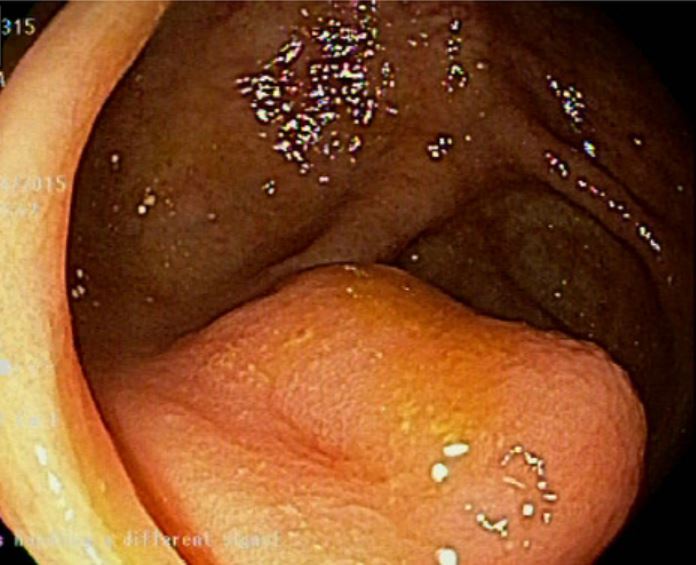

当初、大腸癌と誤診されたS字結腸のMALTリンパ腫

こちらのサイトより引用させていただきました